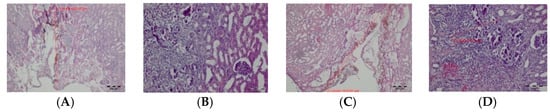

In tissues obtained 14 days after surgery, with both the TDFL and DL the superficial zone of thermal damage was characterized by the presence of thin strands of fibrous connective tissue. Where the laser beam was perpendicular to the surface of the organ, the remains of the exudative phase (in the form of brown homogeneous masses) were present, along with the remains of carbonized tissues. From the edges, the wound was filled with a semicircular fibrous connective tissue with the remains of carbonized necrotic structures and associated inflammatory cells, forming the deeper zone of thermal damage. This band was sharply demarcated from the normal kidney parenchyma. On the border with the normal kidney cortex, focal disappearing necrotic changes were visible (Figure 6). Both the superficial and total zones of thermal damage were deeper after using the DL (Table 2).

Figure 6.

Zones of thermal damage in the renal cortex on day 14 after cutting the kidney with TDFL and DL: (A,B) superficial zone of thermal damage in renal cortex after cutting with TDFL, magnification: 40×; (C) thermal damage in renal cortex after cutting with DL, magnification: 100×; and (D) deeper thermal changes in renal cortex after cutting with DL, magnification: 100×.